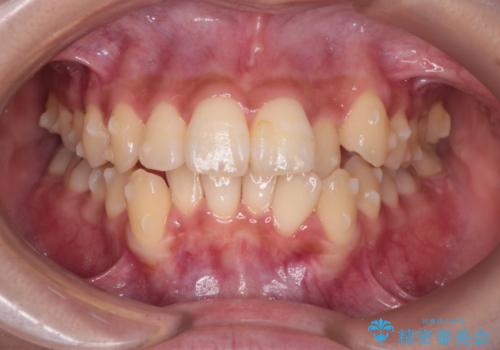

反対咬合を治したい。インビザライン

- 前歯の反対咬合を治したいことを主訴に来院されました。

インビザラインにて臼歯の遠心移動を行いながら、スペースを作り反対咬合を改善することができました。